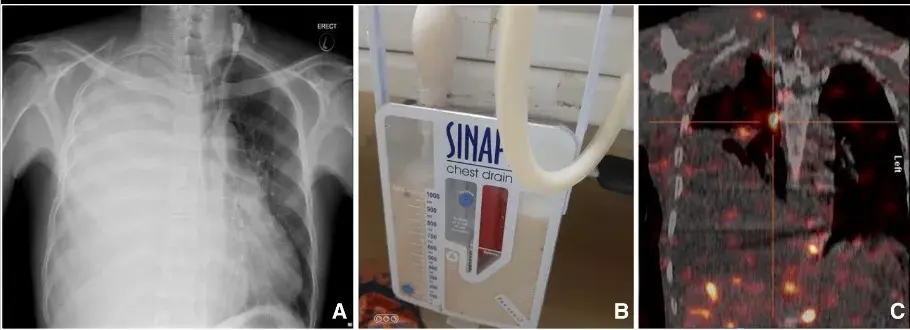

Radiografia e TC de tórax mostraram um derrame pleural volumoso a direita (imagem abaixo).

Realizado análise de toracocentese que evidenciou **concentração elevada de triglicerídeos**, sendo excluído a possibilidade de tuberculose e neoplasias após ampla investigação.

Foi realizado o diagnóstico de quilotórax e o paciente submetido a toracoscopia com ligadura do ducto linfático direito e resolução do quadro.

A-Rx de tórax indicando derrame pleural volumoso a direita. B-Drenagem de liquido quiloso. C-TC tórax com radioisótopo radioisótopo 99mTc indicando vazamento linfático hemitórax direito.